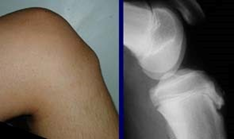

- Palpable & painful lump below the knee

Diagnostic procedure

- The diagnosis is based on typical clinical findings (see clinical presentation).

- Radiographic examinations of both knees to rule out the possibility of tumors, fractures, ruptures or infections.

- Sonographic examination can also be used: cartilage and bony surface, the patellar tendon, soft-tissue swelling anterior to the tibial tuberosity, and fragmentation of the tibial tuberosity.